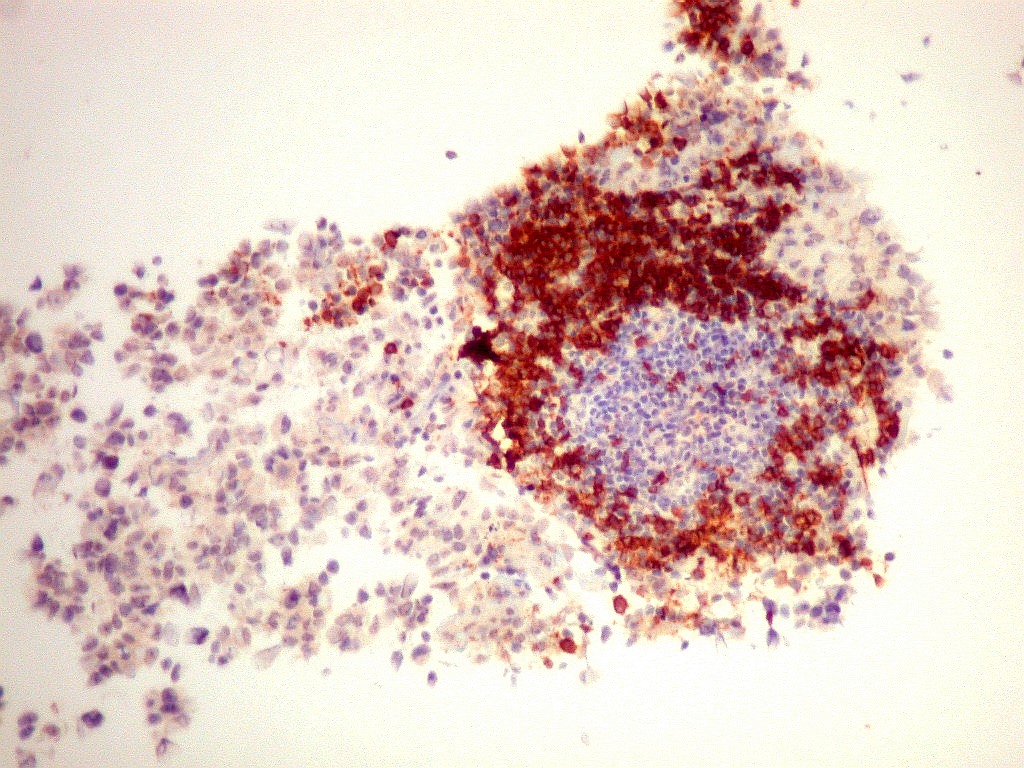

Tumor teratóide rabdóide atípico de III ventrículo.

7.  CD3, CD20, CD68, CD34

CD3.      Positivo nos linfócitos T, negativo nas células neoplásicas.

CD20.      Positivo nos linfócitos B, negativo nas células neoplásicas.  No folículo linfóide presente na amostra, as células centrais são de linhagem T, e as células B concentram-se na periferia.  Células do ATRT não se marcam.